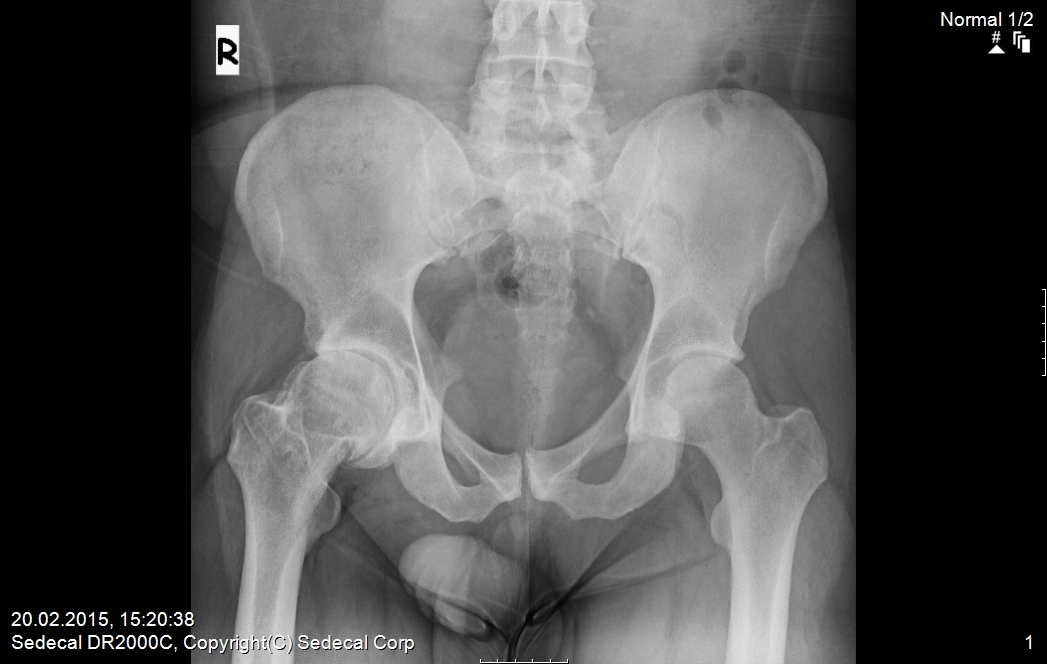

Клинический наблюдения и методы. Под нашим наблюдением с 2008г. по настоящее время находилось 172 пациента с коксартрозом 1-2 стадии в возрасте от 26 до 72 лет, с давностью заболевания от 1 до 20 лет. Мужчин было 51 (30%), женщин 121 (70%).

У 674 пациентов (43 %) отмечено сочетание коксартроза с остеохондрозом. Двухстороннее поражение тазобедренных суставов наблюдалось в 29% случаев.

На рентгенограммах тазобедренный сустав сохраняет нормальную форму, суставная щель умеренно или неравномерно сужена с субхондральным склерозированием костных суставных поверхностей, непостоянными краевыми костными разрастаниями (I стадия).

Рентгенологически суставная щель может быть равномерно или неравномерно сужена, ацетабулярная суставная впадина уплощена, присутствуют явления субхондрального склероза, краевые костные разрастания. Конфигурация головки бедренной кости, как правило, не нарушена (II стадия).

В подавляющем большинстве случаев диагноз коксартроза ставится при рентгенографии, где видны изменения формы и структуры костей, составляющих тазобедренный сустав. Однако рентгенографически в ряде случаев затруднительно зафиксировать ранние проявления артроза, так как хрящевая ткань суставных поверхностей на рентгеновских снимках не отображается и мы можем судить о дегенеративном процессе, когда он достаточно выражен, вызывая изменения ширины просвета рентгеновской суставной щели.